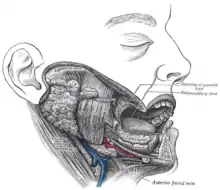

Mouth & Pharynx

Digestion starts in the oral cavity. Food is taken into the mouth; as it is masticated by the teeth, it is mixed with saliva from the parotid, sub-mandibular, and sublingual glands. Saliva contains amylase and lipase enzymes, which are mixed with the food. Because these enzymes are deactivated on reaching the stomach, salivary action is greater when food is more thoroughly masticated. When mastication is complete, the food is swallowed; this is a three-part process, but only the first part is under voluntary control. (see Motility). The epithelial lining of the mouth and pharynx is non-cornifed squamous epithelium.